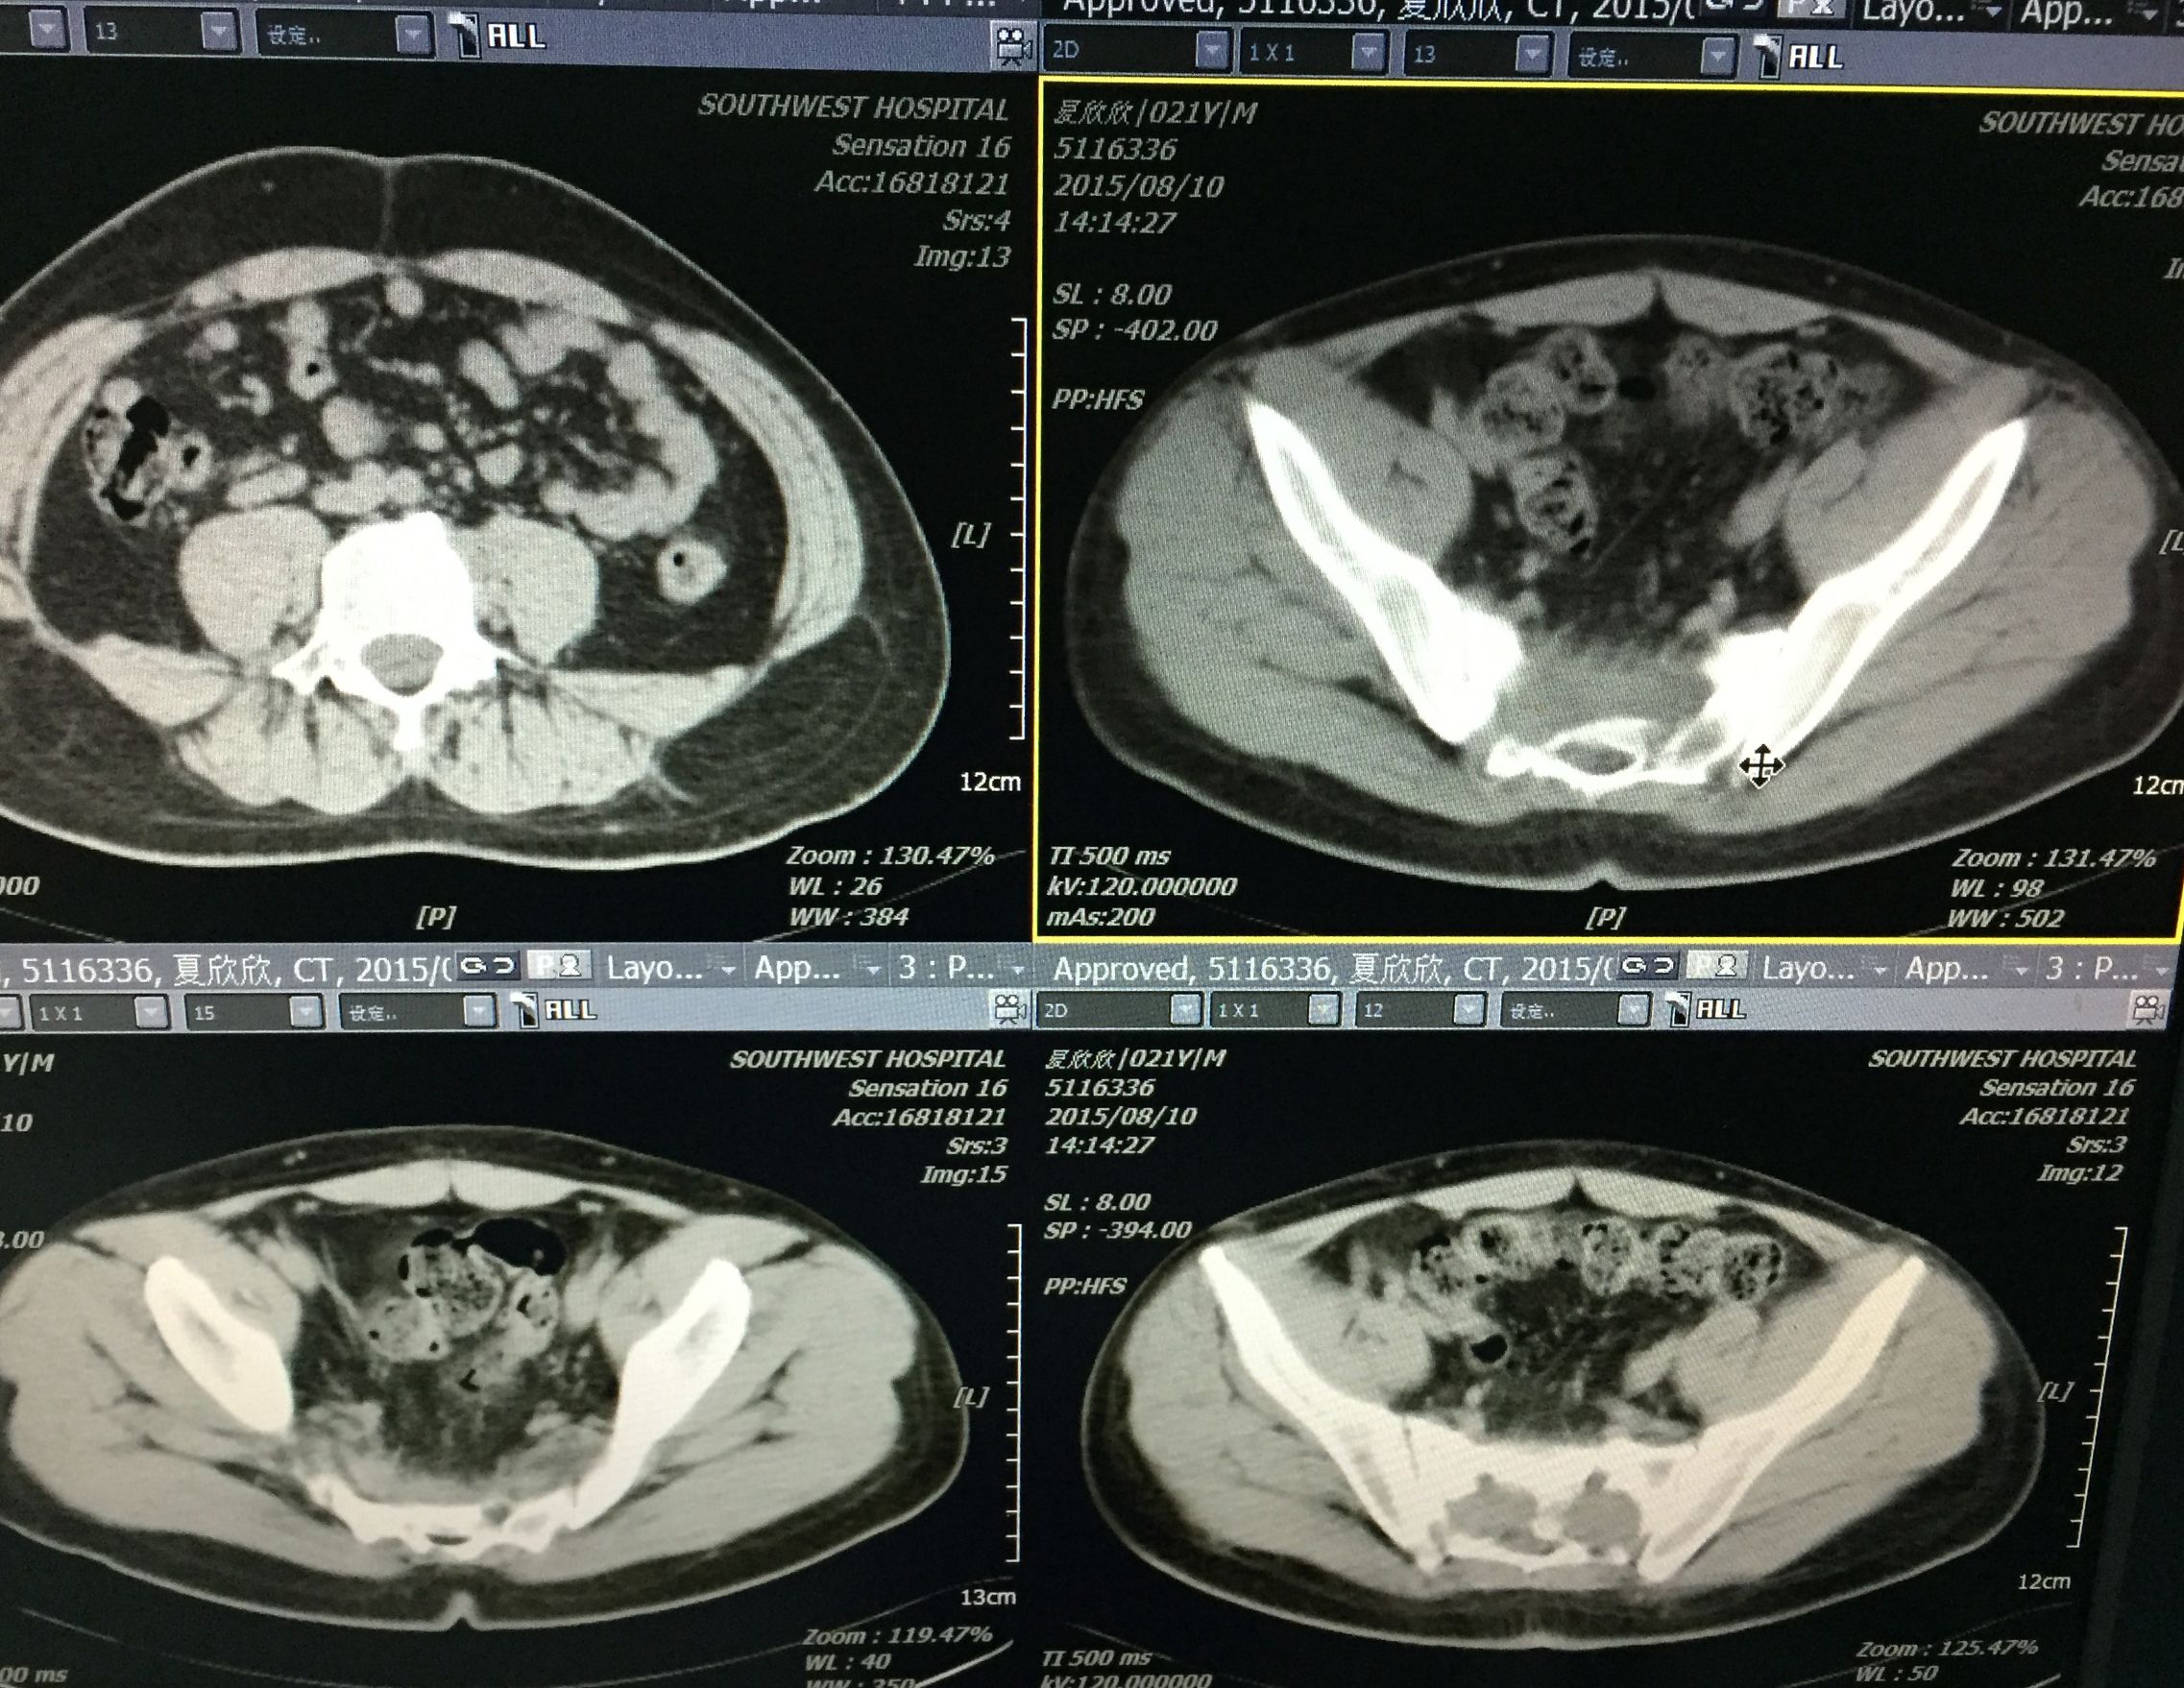

患者 29岁 盆腔及大腿根部多发结核脓肿(如图)

治疗方案充分穿刺置管引流+抗痨治疗

在门诊进行CT引导下穿刺引流术,植入五根引流管(如图白色条状物)